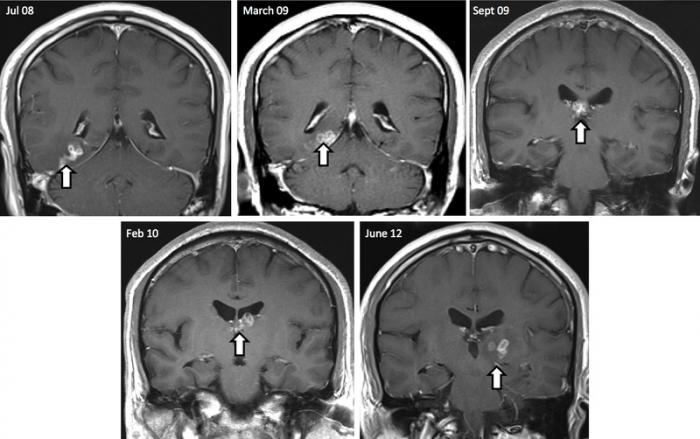

Două scanări cerebrale realizate la interval de 4 ani arată modul în care un vierme lung de 1 cm s-a deplasat prin creierul unui bărbat, înainte de a fi înlăturat în urma unei operaţii.